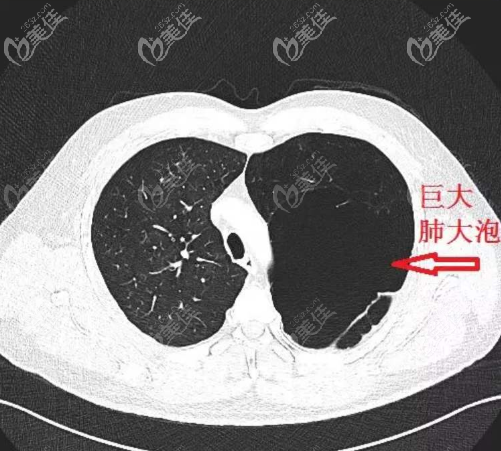

隆鼻取肋软骨时容易戳破胸膜引起气胸,这是真的吗?

b1546 G0 V0

取肋软骨做隆鼻手术,比较大的一个风险就是可能会发生气胸,这让很多人望而却步,那么到底容不容易发生气胸呢?我们一起来看看!